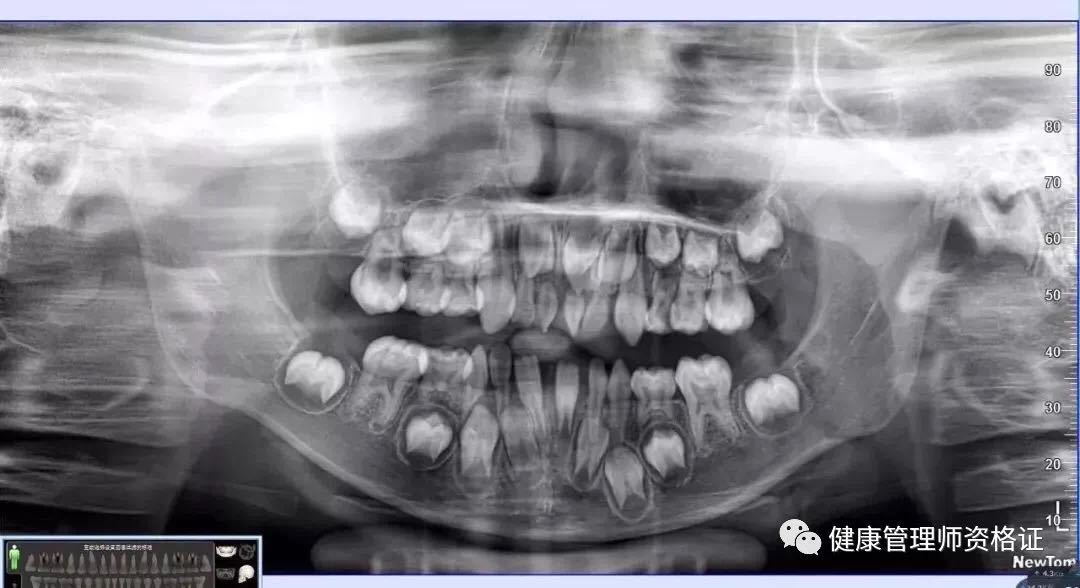

(1) 全景曲斷片

以檢查全口牙齒為目的,全景曲斷片可以觀察到全口牙的形態、位置、頜骨等情況,比如乳牙下方是否有恒牙牙胚在發育、牙頜的畸形程度等等。

想要矯正牙齒的小朋友,以上兩項牙片一定要拍哦~